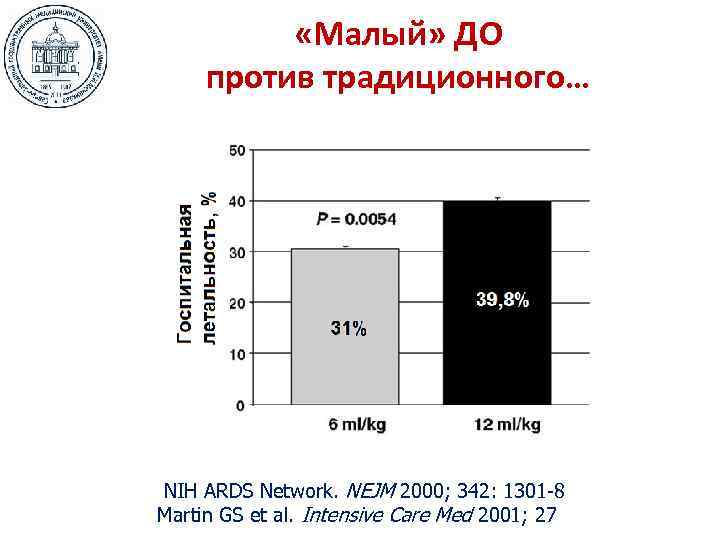

«Малый» ДО против традиционного… NIH ARDS Network. NEJM 2000; 342: 1301 -8 Martin GS et al. Intensive Care Med 2001; 27

«Малый» ДО против традиционного… NIH ARDS Network. NEJM 2000; 342: 1301 -8 Martin GS et al. Intensive Care Med 2001; 27